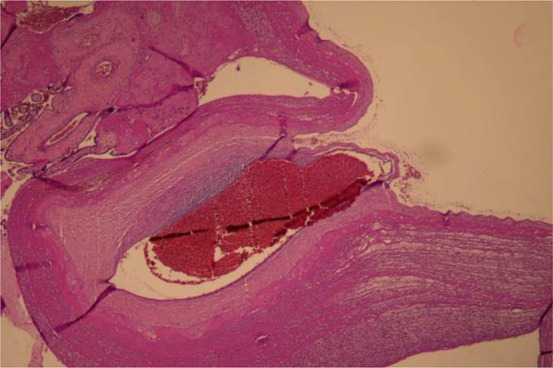

Results: The study included 20 mother-neonate pairs. The mean maternal age was 34±3.6 years, and all mothers received Sinopharm vaccine as their first and second doses. The last vaccine dose was administered during pregnancy, with 3 mothers receiving it in the first trimester, 9 in the second trimester, and 8 in the third trimester. The histopathological findings in the placental samples included decidual vasculopathy, subchorionic thrombosis, and chronic histiocytic intervillositis. All mothers and neonates, except one pair, were positive for anti-spike antibody.

Conclusion: Multiple abnormal histopathological findings were reported in placenta of vaccinated mothers. However, similar to previous studies, these placental findings are considered mild lesions and have been observed in both vaccinated and unvaccinated mothers.